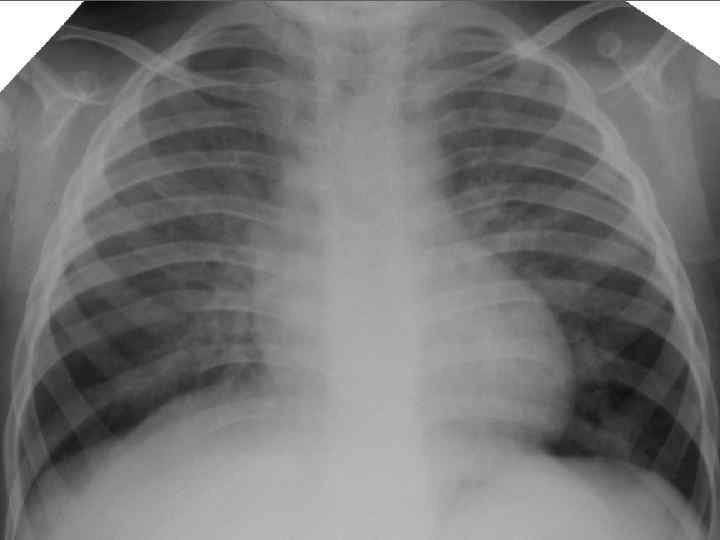

Клинические особенности туберкулеза у взрослых на фоне ВИЧ-инфекции ► ► ► ► ► Внутригрудные аденопатии; Милиарные высыпания; Частое поражение базальных сегментов легких; Относительно редкое поражение каудоапикальных сегментов легких; Распад легочной ткани диагностируется в 2 раза реже; Нередок плевральный выпот; Велика склонность к генерализации туберкулезной инфекции с множественными внелегочными локализациями. Присоеднинение туберкулезного менингита; МБТ в мокроте выявляются одинаково часто у ВИЧ негативных и позитивных лиц, по крови МБТ методом посева выделяются у 70% пациентов; При отсутствии признаков локального туберкулеза и неясной лихорадке – посев костного мозга часто дает МБТ+.

Клинико-эпидемиологические особенности туберкулезной инфекции у ВИЧинфицированных и больных СПИДом детей ► Вертикальный путь заражения ВИЧ; ► Ранний возраст; ► Семейные контакты с болеющими туберкулезом в активных фазах; ► Отсутствие вакцинации БЦЖ; ► Выраженный локальный процесс, протекающий с: § бронхолегочными поражениями; § Распадом легочной ткани; § Обсеменением легочной ткани.

Неблагоприятное сочетание ряда обстоятельств: § Ранний возраст; § Тяжелые семейные контакты; § Отсутствие вакцинации - и у свободных от ВИЧ-инфекции детей всегда приводят к развитию локального туберкулеза, протекающего, как правило, ОСЛОЖНЕННО с бронхолегочными поражениями, распадом легочной ткани, диссеминациями.